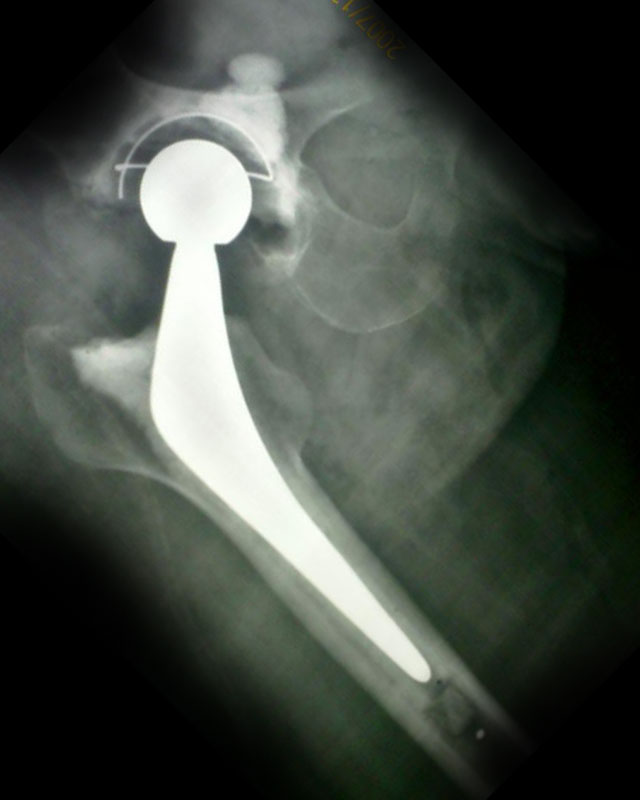

Hip Replacement Surgery

- Cemented, Cementless, Hybrid, Metal On Metal, Ceramic On Ceramic, Total Hip Replacement

- Hip Resurfacing

- Bipolar Hip Replacement